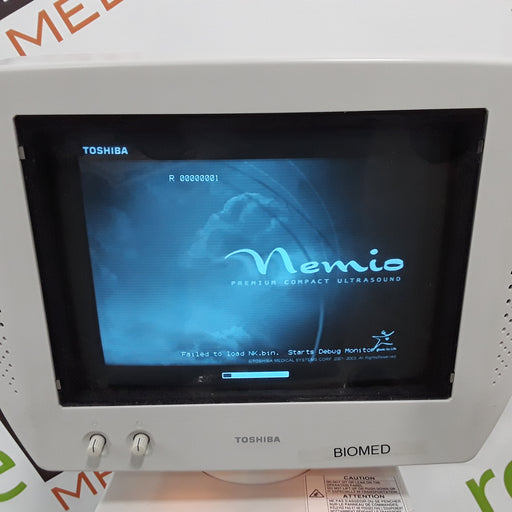

Original price $332.00 - Original price $332.00Original price$332.00$332.00 - $332.00Current price $332.00| /Toshiba Nemio SSA-550A Ultrasound Machine

Functional Condition

NewRefurbishedreLink CertifiedUsedNon FunctionalCosmetic Condition

New in BoxNew out of BoxExcellentGoodPoorOEM: ToshibaMaterial: Nemio SSA-550A Common Name: Ultrasound Machine Software Version: 4.5.000A Accessories: Sony UP-895MD printer Item Weight: 217...